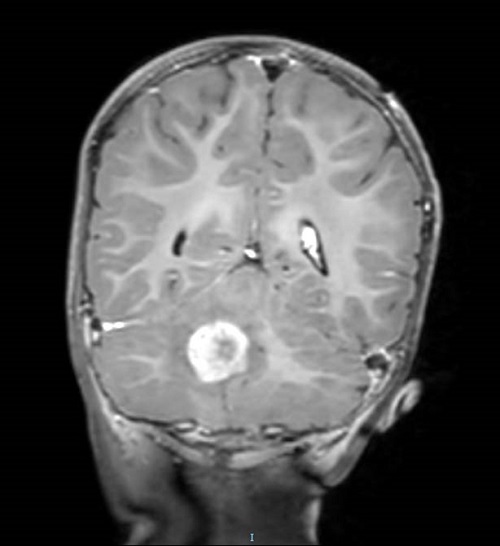

Se realiza una prueba de imagen a los 23 meses de edad, en la que se evidencia una lesión focal intraaxial en la fosa posterior que afecta al cuarto ventrículo, sugestiva de neoformación primaria compatible con ependimoma o glioma de bajo grado (Low Grade Glioma, LGG) (Figura 2, Figura 3 y Figura 4).

Figura 3. Imagen de resonancia magnética en corte transversal donde se visualiza una lesión tumoral infratentorial hemisférica paracentral derecha; comprime la base del 4.º ventrículo sin obstrucción y no produce hidrocefalia obstructiva de 3.º ventrículo ni laterales. Mostrar/ocultar